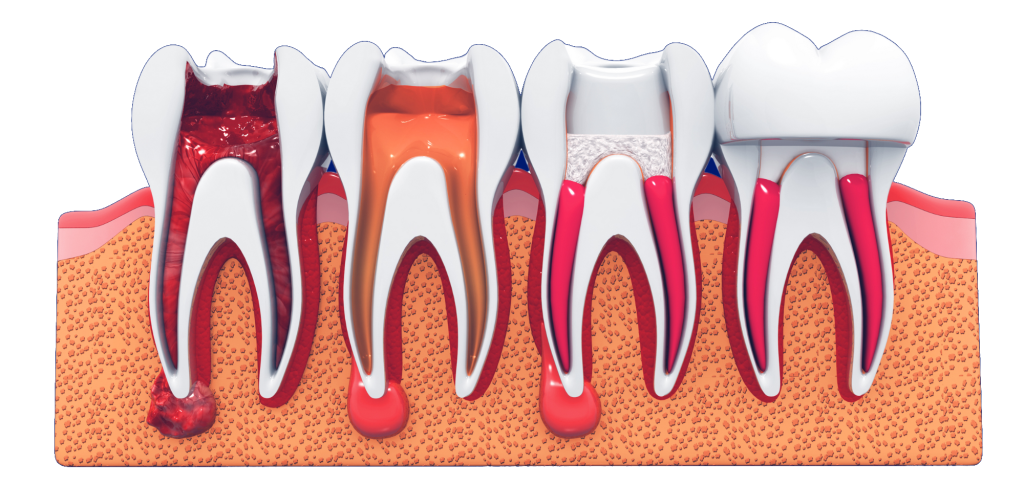

Common dental issues such as decay, cracks or trauma can eventually lead to infection of the pulp – the soft tissue at the core of the tooth. The pulp consists of connective tissue that performs several key functions:

When overwhelmed by bacteria, chemical or mechanical stimuli, the pulp becomes inflamed or infected. This is a condition known as pulpitis, which may progress to pulp necrosis (death of the pulp). When this happens, non-surgical root canal treatment is usually the first line of care to preserve the tooth.

Root canal treatment involves accessing the pulp chamber to disinfect it, by removing infected tissue and microorganisms. Once cleaned, the space is sealed with a durable material to prevent reinfection. This procedure typically requires 1–2 visits or more, depending on the complexity of the root system and the extent of infection. RCT generally has a good long-term prognosis, with multiple studies reporting success rates of 85–95% over 10 years or longer.